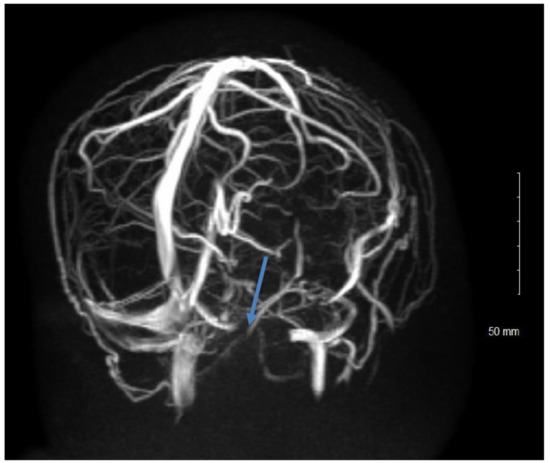

5.2. Signs

- Kohli, A.A.; Vossough, A.; Mallery, R.; Woo, J.H.; Sheldon, C.A.; Paley, G.L.; Digre, K.B.; Friedman, D.I.; Farrar, J.T.; McCormack, S.E.; et al. Magnetic Resonance Imaging Findings in Pediatric Pseudotumor Cerebri Syndrome. Pediatr. Neurol. 2019, 99, 31–39. [Google Scholar] [CrossRef]